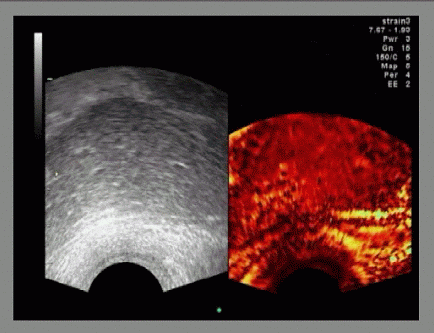

Echtzeit Elastographie: in vivo Prostata mit Histologie Sample 01 (gif)

Echtzeit Elastographie: in vivo Prostata mit Histologie Sample 02 (gif)